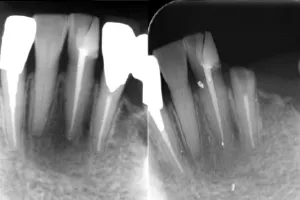

Case.01

治療前

治療中

治療後

治療前後の比較

| 治療名 | 根管治療 |

| 患者様情報 | 76歳 女性 |

| 担当医 | 岸田 義弘 先生 |

| 費用 | 1根管33,000円~ |

| 主訴 | 下の前歯の歯茎が腫れて痛い |

| 治療期間 | 約2ヶ月 (月1〜2回) |

| 治療内容 | 1.歯髄が生きているかどうかの確認 2.根管治療 3.修復治療 4.経過観察 治療の結果腫れもなくなり、歯の移動も戻りました。 |

| 治療のリスク | 術後2~3日後に痛みが出ることあります。術後1年程経過を追って、治癒傾向があれば経過観察、病変の拡大を認めるならば外科的対応になる可能性があります。 |